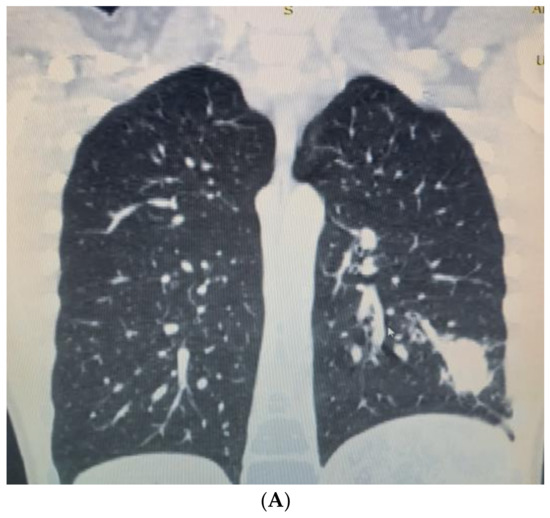

The patient’s complaints persisted, and the child was admitted to the Department of Pediatric Thoracic Surgery for further exams. The condition of the child was stable, with reduced productive cough and reduced vesicular breathing paravertebrally and axillary on the left side of the chest. His hemodynamic was stable, and his abdomen was not tender, without hepatosplenomegaly. Blood and biochemical tests were in the normal range, with slightly increased inflammation markers (leucocytes 11.8 G/L, hemoglobin 137 g/L, hematocrit 0.43 L/L, thrombocytes 404 G/L, CRP 0.59 mg/dL, ASAT 21 U/L, ALAT 13 U/L, creatinine 53 µmol/L). Frontal and chest X-rays revealed atelectasis of the posterior basal segment (Figure 2A,B). A flexible bronchoscopy was performed. The trachea, right main bronchus, and segmental and subsegmental bronchi were without obstruction and pathology. The left main and upper lobe bronchi also were normal. A thick secretion was found in the left lower lobe bronchus, and a bronchoalveolar lavage was performed. Stenosis and obturation resulting from hypergranulation were found in the segmental and subsegmental bronchi of the posterior basal segment (LB10). Recanalization of the LB10 was performed with histopathology and microbiology samples. After five days, a second flexible bronchoscopy was made. Poor improvement was marked by persisting stenosis and obturation of LB10. Again, a biopsy and recanalization with new samples were performed. The microbiology was negative, and the histology showed acute bronchitis. Antibiotics (Ceftriaxone) and symptomatic treatment (Pulmicort inhalations) were extended during the entire hospital stay. The patient was discharged on the 7th day and transferred back to the Department of Pediatric Pulmonology for prolonged treatment.

Figure 2. (A). Frontal chest X-ray—atelectasis of the posterior basal segment. (B). Lateral chest X-ray.